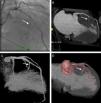

A Figura 2 apresenta a anatomia das artérias septais (seta) por coronariografia invasiva (A) e por TC (B-D), evidenciando a relação das septais (seta) com a cavidade ventricular (C) e o miocárdio hipertrofiado (B e D).